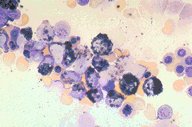

ANLL-M-2 (myeloperoxidase stain)

This slide is a high dry photomicrograph of a

bone marrow aspirate which has been reacted

with the myeloperoxidase stain. The patients's

diagnosis is acute non-lymphoblastic leukemia,

FAB class M-2. Many blasts in this field have the

dark granules of myeloperoxidase positivity.